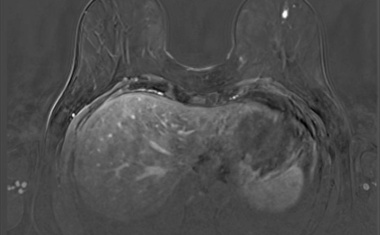

3D-Modell eröffnet Ansatzpunkte für Therapien von Hirnmetastasen nach Brustkrebs

Forscher des Instituts für Klinische Neurobiologie am Universitätsklinikum Würzburg haben ein 3D-Modell entwickelt, das zeigt, wie sich das neuronale Netzwerk durch Hirnmetastasen nach Brustkrebs verändert.